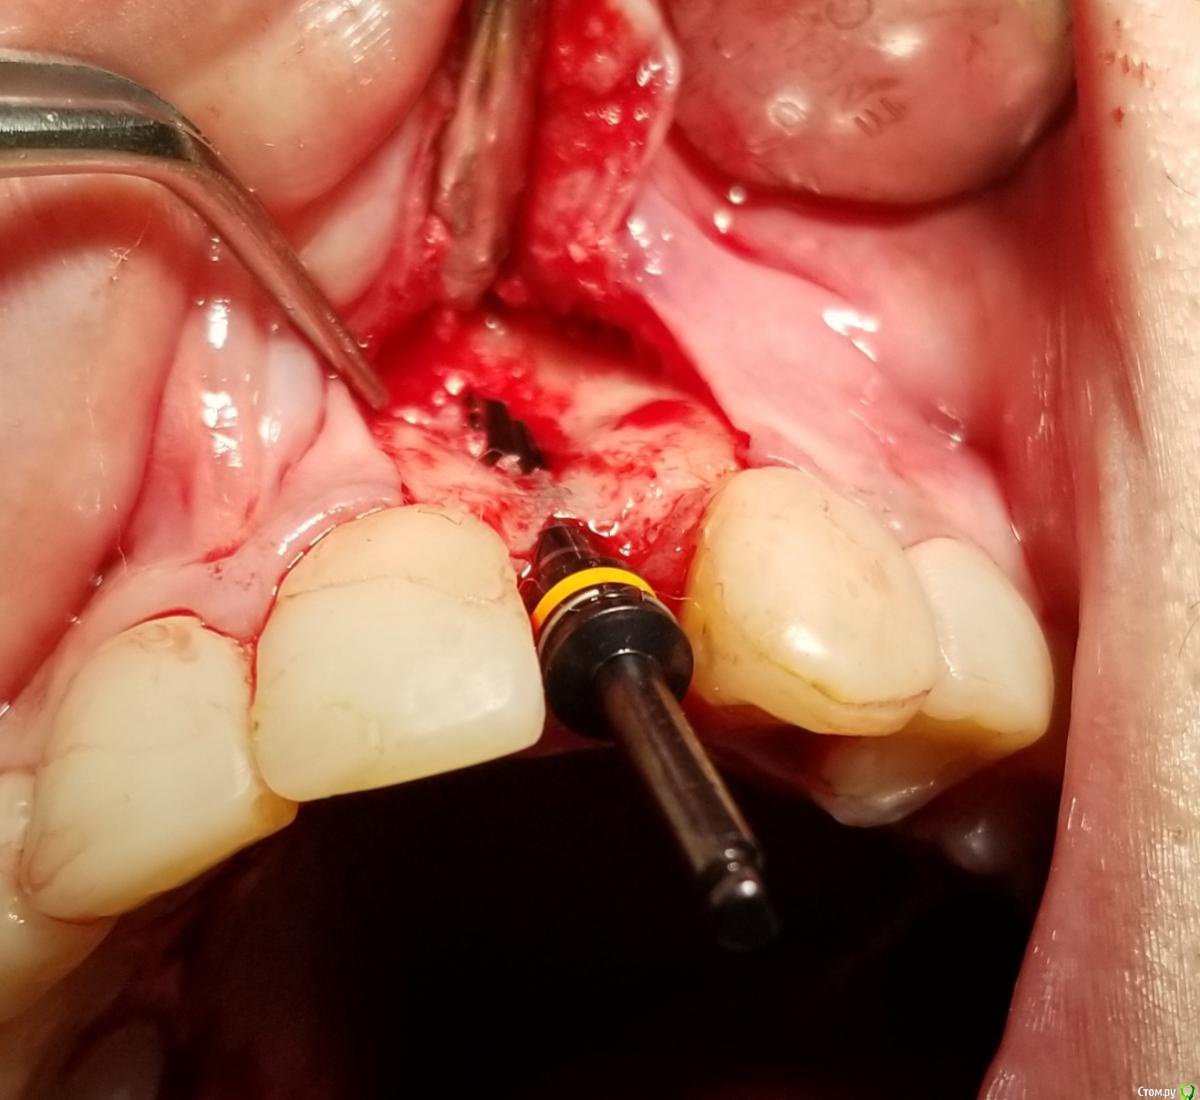

АнтонТЛТ Опубликовано 18 сентября, 2018 Поделиться Опубликовано 18 сентября, 2018 У шейки недопаковано было, апикальной лучше фиксировать, вертикальные разрезы надо не так делать. Спейсер неродной что ли? 6 Ссылка на комментарий

Bier Опубликовано 19 сентября, 2018 Поделиться Опубликовано 19 сентября, 2018 какой апатос был? кортикал или микс? Апикальная фиксация обязательна. По всем пунктам согласен с Антоном.Вертикальные разрезы ужасные. Надо резать через центр сосочка, ни в коем случае нельзя по зениту разрезать. 1 Ссылка на комментарий

АнтонТЛТ Опубликовано 20 сентября, 2018 Поделиться Опубликовано 20 сентября, 2018 имплант с полированой шейкой, эго не желательно сильно погружать под кость.В инструкциях производителя этот тип мембран не предназначен для апекальной фиксации, есть мембраны с проререзями под винты но у нас таких не продают.Только шейка не полированная, а фрезерованная. Мембраны с прорезями это более новый вид. Мембраны без прорезей можно пробивать пином или пин/винт крепить между ножек. В вашем случае, если не прибивать, то надо было мембрану лучше загнуть или взять больший размер, чтобы мембрана опиралась на кость апикально. 2 Ссылка на комментарий

an_ver Опубликовано 29 сентября, 2018 Поделиться Опубликовано 29 сентября, 2018 У шейки недопаковано было, апикальной лучше фиксировать, вертикальные разрезы надо не так делать. Спейсер неродной что ли?При таком виде верт.разрезов практически всегда ресессия обеспечена Ссылка на комментарий